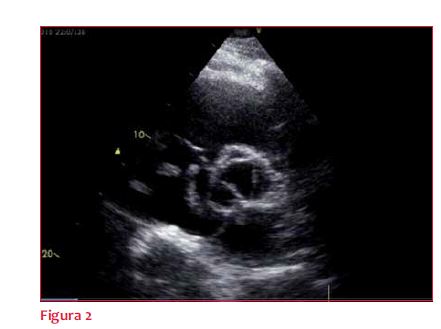

Como parte de la valoración se solicita ecocardiograma Doppler transtorácico (ETT) (figura 2) que mostró trombo blando móvil en aurícula derecha (AD) que se insinúa a través del septum interauricular (SIA), lo que configura un trombo en tránsito (TT) a través de un foramen oval permeable (FOP). No se observa pasaje de contraste salino de izquierda a derecha (el trombo oblitera el FOP). Hipertrofia ventricular izquierda concéntrica moderada. Alteraciones de la motilidad septal atribuibles a sobrecarga de presión en cavidades derechas (D-shape). Fracción de eyección de ventrículo izquierdo: 60%. Cavidades derechas dilatadas. Presión sistólica en arteria pulmonar: 40 mmHg. Disfunción sistólica del ventrículo derecho (VD).